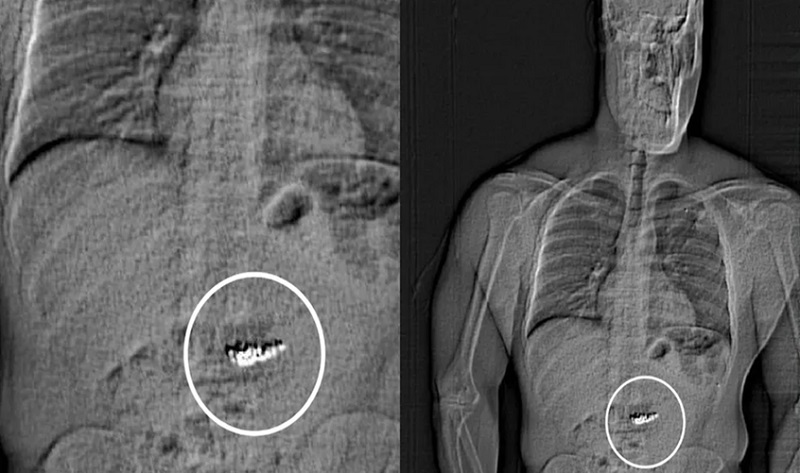

وبعد مطاردة قصيرة، قبضت الشرطة الأميركية على الرجل بتهمة العصيان لأوامرها. وعند إخضاعه للفحص الطبي في مركز الاحتجاز، اكتشف المسؤولون وجود الأقراط داخل معدته.